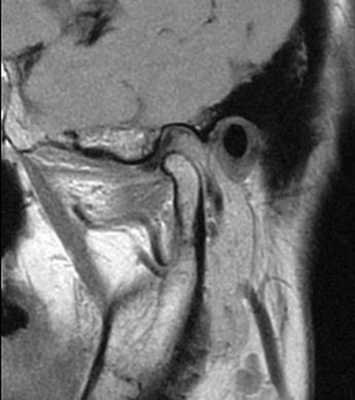

69-летняя пациентка с основными жалобами на боли в проекции челюсти, ограниченное открытие полости рта и невозможностью выдвинуть челюсть вперед обратилась за стоматологической помощью. Со слов пациентки ее симптомы начали развиваться около 6 месяцев назад: именно тогда она заметила, что ей трудно выдвигать челюсть вперед, чтобы посвистеть к своей собаки. По данным анамнеза на протяжении около 50 лет больная отмечала «выскакивание» и «пощелкивание» челюсти с левой стороны, и данные симптомы прекратились приблизительно в то время, когда ей стало трудно выдвигать нижнюю челюсть вперед. В ходе клинического осмотра было обнаружено, что максимальная величина межрезцового расстояния составляла 35 мм, при этом в ходе максимального открытия полости рта челюсть несколько смещалась влево. После массажа и растяжения левой жевательной мышцы и сустава снизилась интенсивность болевых ощущений, однако объем движений не увеличился. Таким образом был поставлен диагноз левостороннего смещения суставного диска без сопровождающейся редукции ВНЧС. Пациентка была направлена на магнитно-резонансную томографию (МРТ), и для исследования локализации и состояния диска при открытом и закрытом рте. Данные МРТ позволили установить, что с левой стороны отмечалось переднее смещение суставного диска в обеих положения, что также подтверждает диагноз смещения без редукции (фото 1-4).

Фото 2. МРТ-скан правого ВНЧС при открытом состоянии рта: визуализация положения диска.

Фото 3. МРТ-скан левого ВНЧС при закрытом состоянии рта: визуализация переднего смещения диска без редукции.